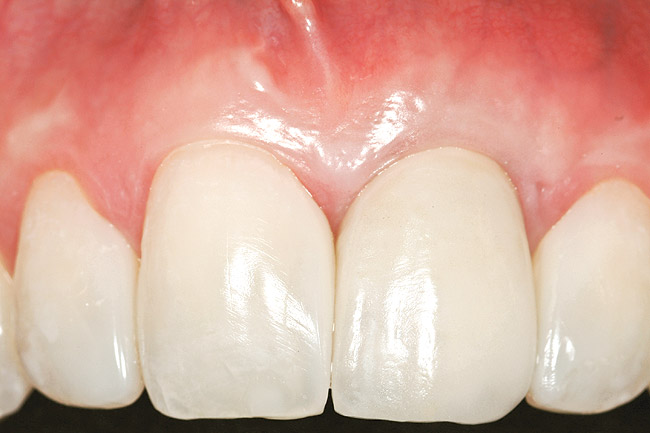

The 2-month postoperative view can be seen in Figure 13 through 15. Note the color match of the tissue, balance of the facial heights of contour, and zones of attached keratinized tissue present.

Figure 14  Case One The 2-month postoperative view, maxillary anterior.

Figure 14